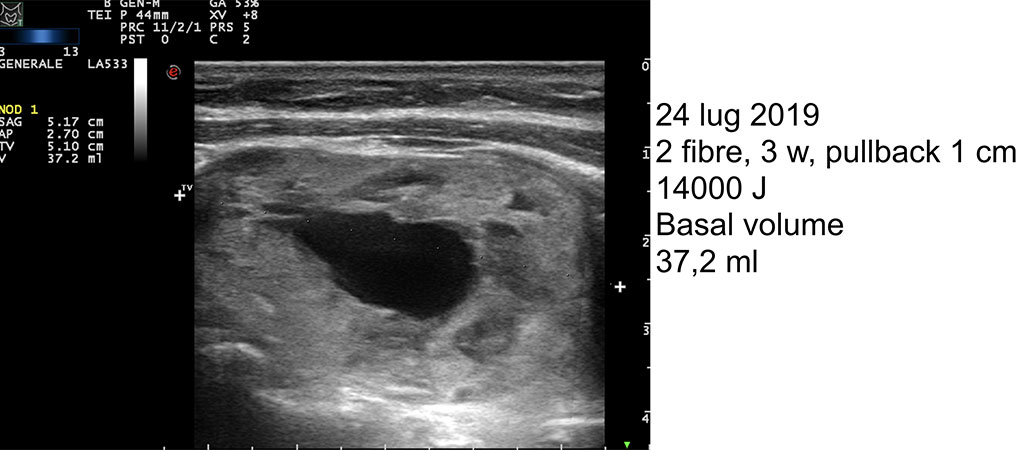

Per i noduli tiroidei benigni, l’efficacia del trattamento consiste nella riduzione progressiva del nodulo tiroideo nel tempo (diminuzione del volume di almeno il 50% rispetto al volume basale un anno dopo il trattamento) con conseguente risoluzione / riduzione dei sintomi e miglioramento della qualità della vita dei pazienti trattati. Il monitoraggio dei pazienti sottoposti a termoablazione laser e le pubblicazioni scientifiche hanno dimostrato che una singola sessione ModìLite assicura risultati duraturi. Per le lesioni maligne il trattamento produce una completa ablazione della massa con un margine di sicurezza sufficiente per raggiungere la sua distruzione totale.

Gallery di alcuni casi trattati con ModìLite, il nuovo trattamento percutaneo laser dei noduli tiroidei

1) Nodulo tiroideo compressivo del lobo destro a struttura mista di 8,4 ml trattato con ModìLite

2) Lo stesso nodulo tiroideo dopo un anno dal trattamento mostra un volume di 1,1 ml, pari a 87% di riduzione volumetrica